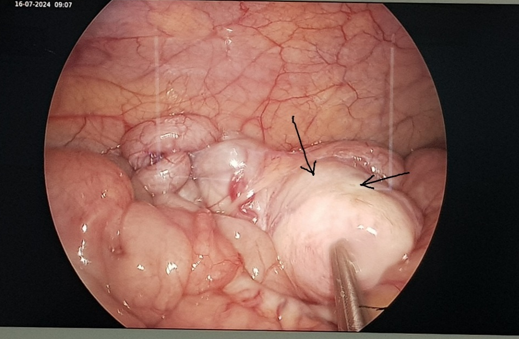

Nang ruột đôi trong mổ nội soi